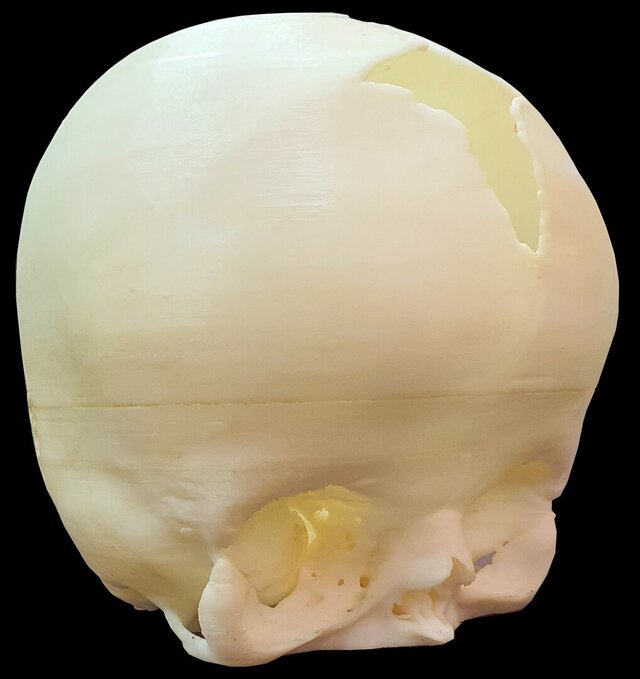

# Advanced 3D Modeling and Printing for Neonatal Apert Syndrome I led and supervised a dedicated team in reconstructing a highly precise neonatal cranium model for a patient affected by Apert syndrome, leveraging advanced HRCT data and parametric modeling techniques. Through meticulous analysis and collaborative innovation, we converted complex imaging data into a detailed 3D model that accurately represented the unique cranial anatomy of the patient. The model was then expertly 3D printed, serving as a critical surgical aid to enhance preoperative planning and precision during the procedure. This achievement underscores the transformative potential of integrating medical imaging with cutting-edge modeling and printing technologies to address complex craniofacial conditions, setting a benchmark for future interdisciplinary collaborations. For example, the detailed 3D representation allowed surgeons to simulate surgical approaches, reducing risks and ensuring better outcomes for the patient.